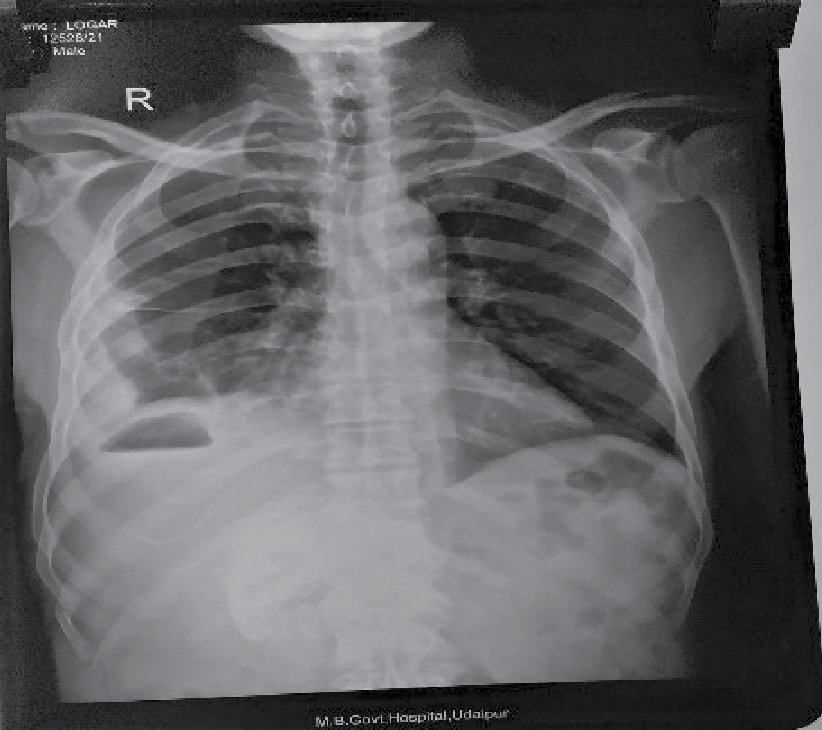

On examination, patient was febrile and abdominal tenderness was present over right hypochondrium; bowel sounds were present. His pulse rate was 110/min, blood pressure was 110/70 mmHg and respiratory rate was 20/min. Investigations done were as follows: Hemoglobin - 7.3 g/dL, total white blood cell count - 6900/cc, neutrophil - 50% and lymphocytes - 19.2%. His total bilirubin and direct bilirubin were normal. Serum glutamic oxaloacetic transaminase (SGOT), serum glutamic pyruvic transaminase (SGPT) and alkaline phosphatase (ALP) were increased around 10 times. His total protein and albumin were below normal. Chest X-ray and X-ray flat plate abdomen (FPA) in erect posture showed gas shadow under right hemidiaphragm (Figs. 1 and 2).

Figure 1. Chest X-ray PA view shows gas under right hemidiaphragm.

The chest X-ray and X-ray FPA are abnormal in approximately 50% of the cases, with findings reflecting subdiaphragmatic pathology, such as an elevated right hemidiaphragm, right pleural effusion or atelectasis. Occasionally, there may be left-sided findings in the case of an abscess in the left lobe of the liver.

In this case, liver abscess filled with pus and having air fluid level visible in CECT abdomen, was responsible for gas under right dome of diaphragm in chest X-ray and X-ray FPA in erect posture.